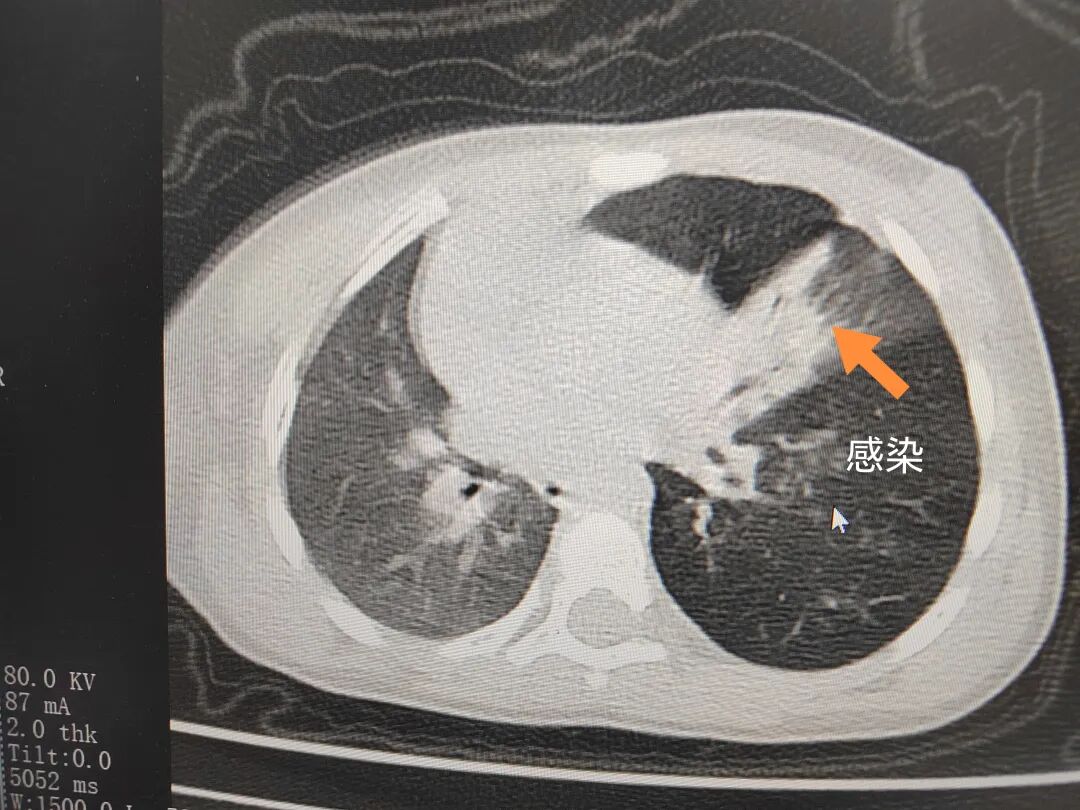

三天后(11月13日),趙寶出現(xiàn)高熱、咳喘加重,家長著急了,再次帶他來到醫(yī)院。CT檢查顯示左肺過度充氣,左肺上下葉支氣管主干見不規(guī)則高密度影,左肺上葉可見大片狀密度增高影,縱隔窗實(shí)變,提示為“左側(cè)支氣管內(nèi)異物并繼發(fā)性改變,左肺上葉舌段肺膨脹不全”。

市二院小兒呼吸內(nèi)科副主任楊亞娟介紹,異物誤入氣道可能導(dǎo)致氣道阻塞,嚴(yán)重時(shí)可引發(fā)窒息,甚至危及生命。若異物進(jìn)入支氣管,造成不完全堵塞,可引起阻塞性肺氣腫;如完全堵塞支氣管,則可能導(dǎo)致肺組織萎縮,形成肺不張。此外,若異物存留時(shí)間較長,或?yàn)橹参镄援愇铮菀缀喜⒓?xì)菌感染,產(chǎn)生膿性分泌物,進(jìn)而發(fā)展為肺炎。她強(qiáng)調(diào),盡早診斷并取出異物,是減少并發(fā)癥、降低病死率的關(guān)鍵。